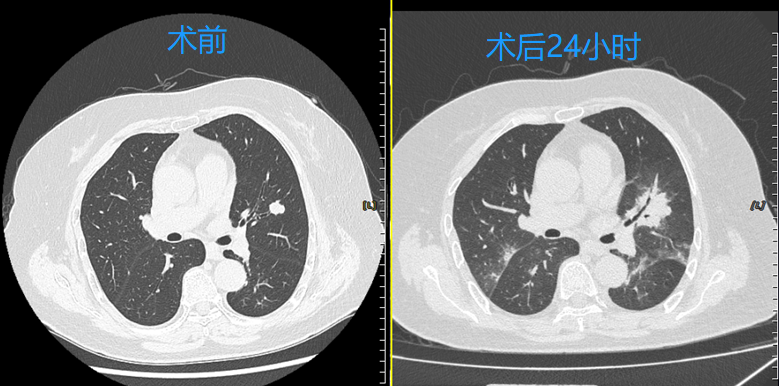

患者为女性,70岁,确诊气管腺样囊性癌两年并出现双肺多发转移瘤,其中一个病灶在近3个月随访中出现快速生长,患者和家属要求积极治疗,控制肿瘤生长及转移速度。考虑到腺样囊性癌对于传统放化疗等治疗不敏感,经多学科团队(MDT)综合评估后,呼吸与危重症医学科介入团队决定采用国际前沿的经支气管镜冷冻消融术,精准消融肿瘤病灶,最大限度保护正常肺组织。

快速康复:患者术后当日即可下床活动,术后24小时复查胸部CT,冷冻消融区域覆盖结节病灶,3天后顺利出院,生活质量不受影响。